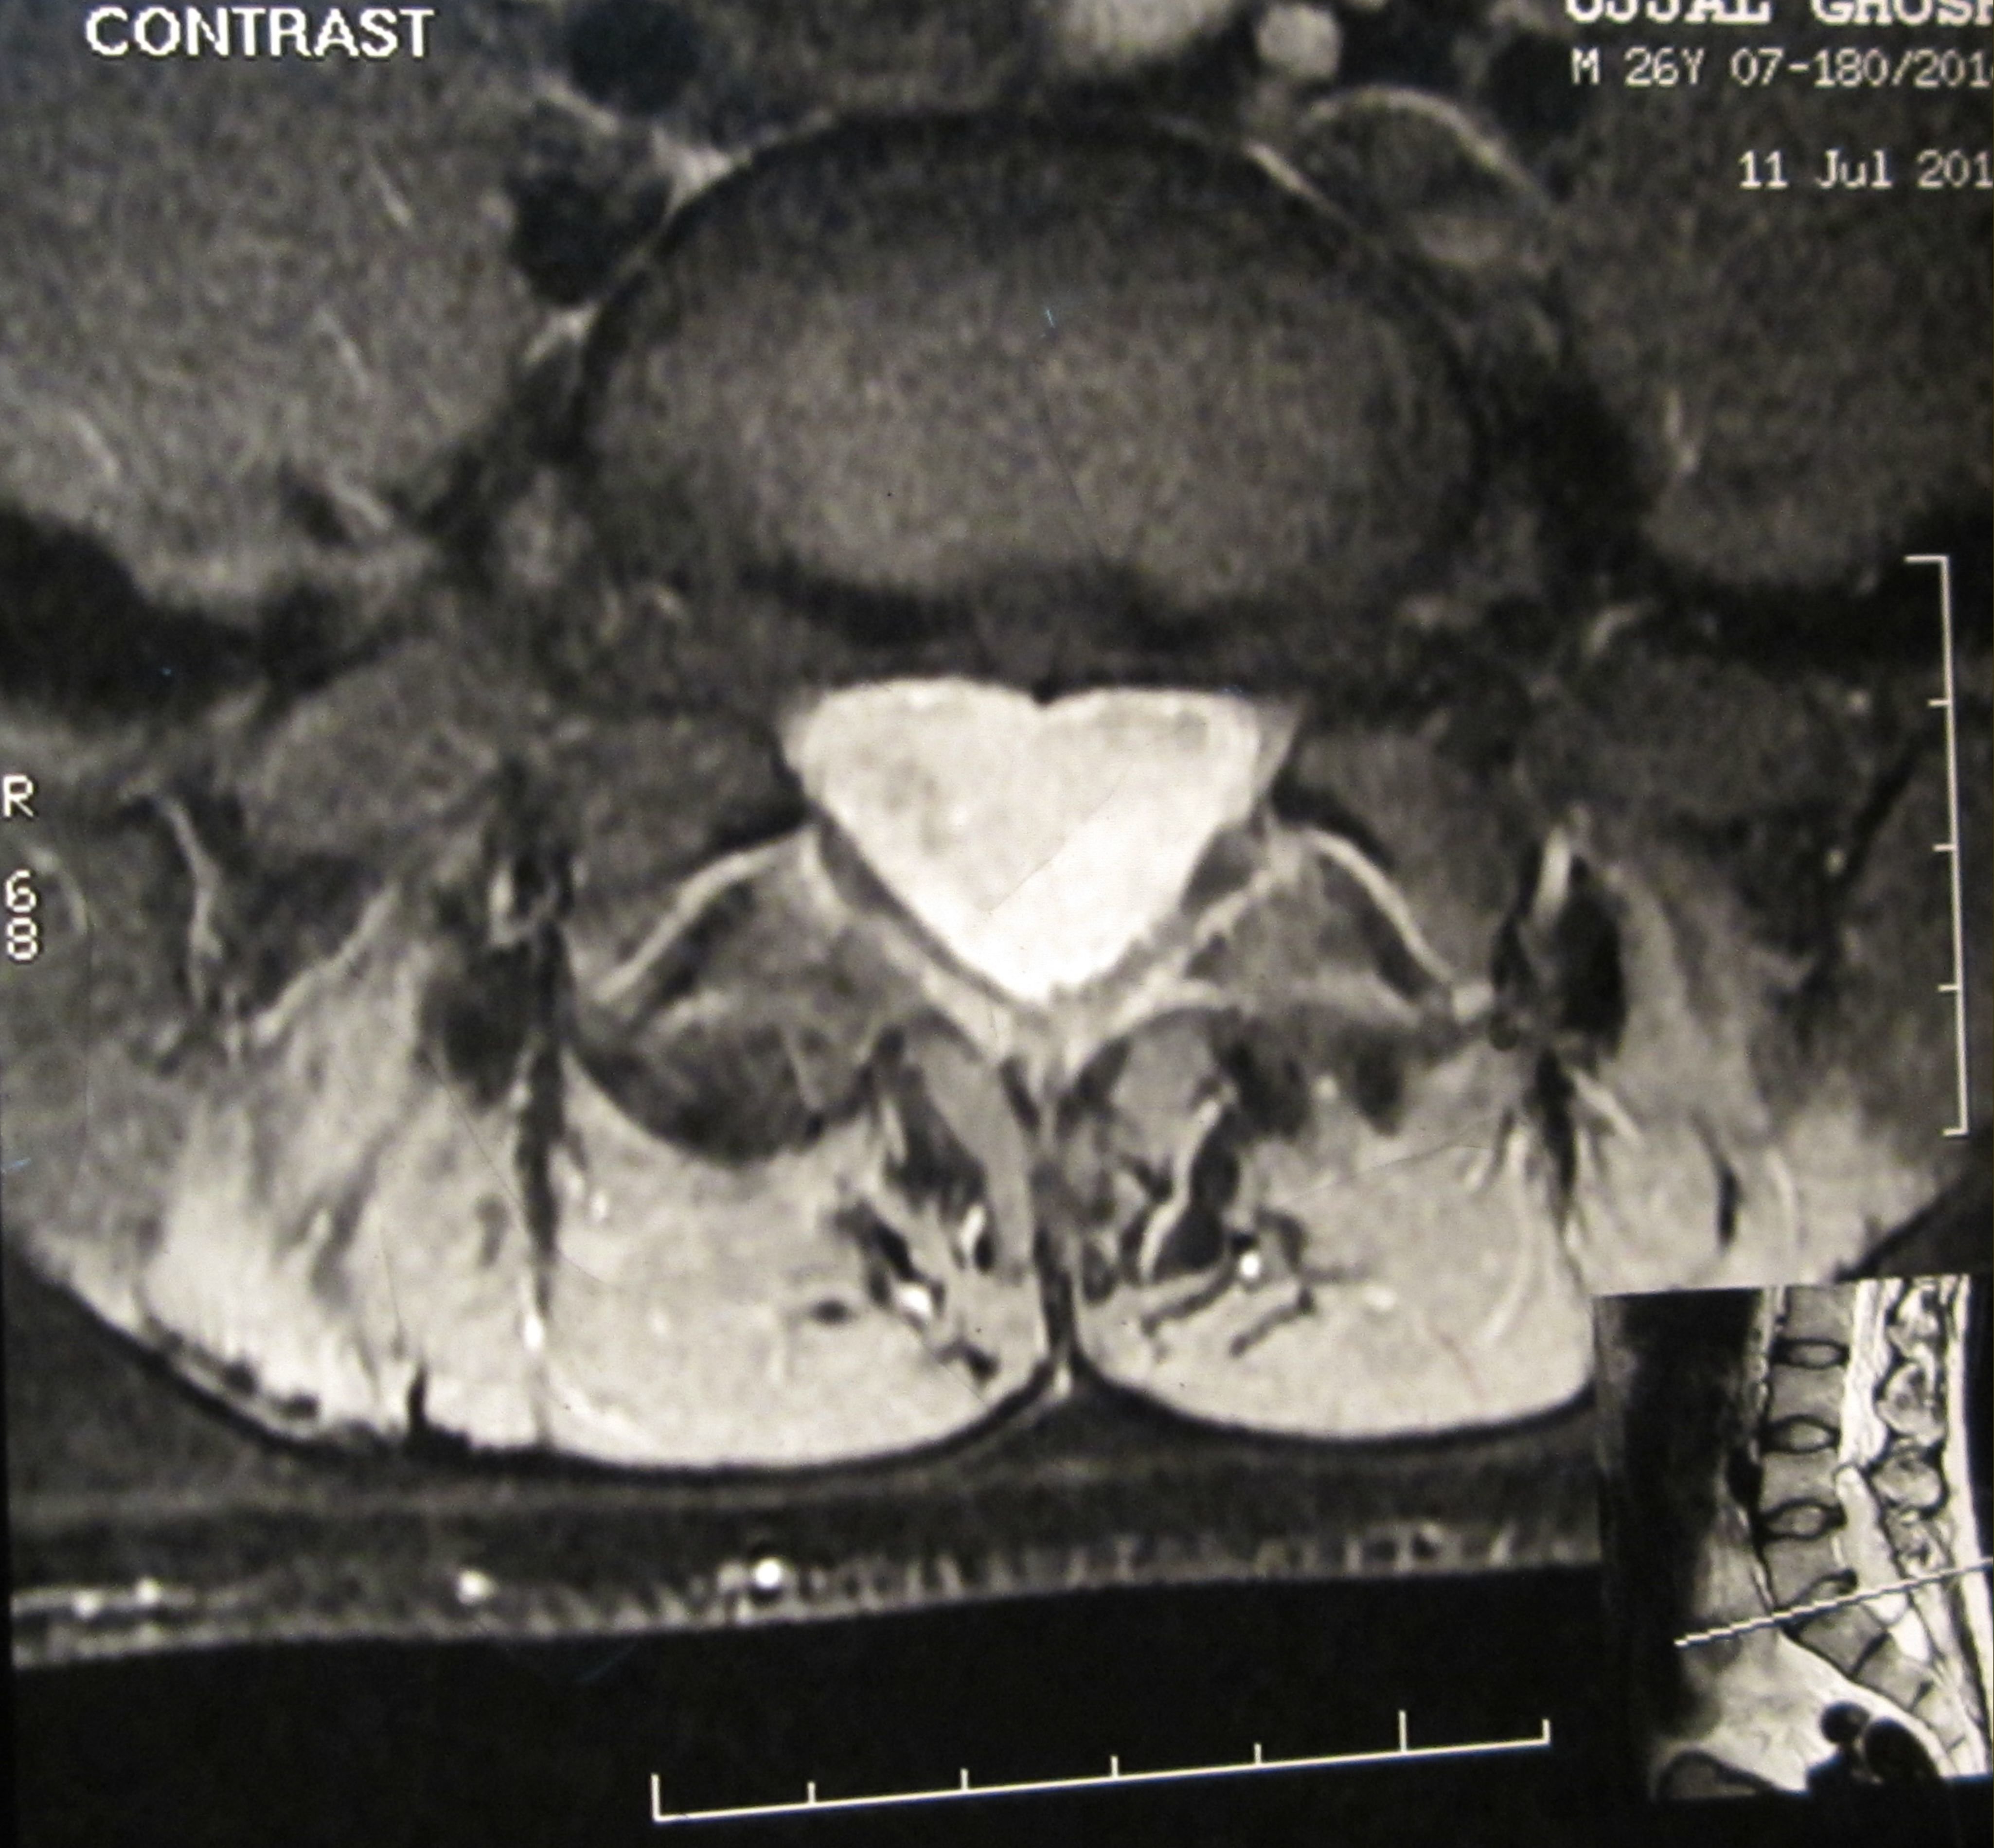

Filum terminale paraganglioma is a rare tumour with usual short segment spinal involvement (one or two segments) as described in various literatures. It can also present with long segment spinal involvement as in our case, the tumour has involved L4 to S1 segments. Prognosis of filum terminale paraganglioma is excellent after total excision as it is classified under WHO grade I tumor. Nonetheless, after subtotal removal, tumour recurrence can occur. Even such an extremely rare entity with a larger spectrum of presentation can be treated successfully by total removal of the tumour. Here we present a fi lum terminale paraganglioma which was diagnosed after histopathology and immuno-histochemistry. Patient made a full recovery after tumour removal.